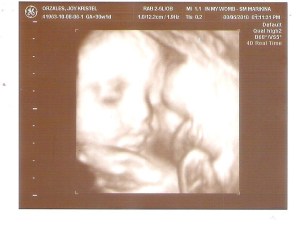

more or less 2 months na lang and baby will say hello to the world..last august 6, we had 3d4d ultrasound para icheck si baby.,we were so excited before going to the clinic..i though hindi matutuloy ang ultrasound (just to expect the worst)..but no,,we went to SM marikina (in my womb) to have the ultrasound.,the procedure lasted for about 30 minutes..baby ria smiled many times especially when me and dann tried to talk to her..she’s so pretty khit sa 4d pa lang.,kuhang kuha sa daddy niya ang ilong at lips (i thought skn ang lips pero it turned out na kay dann nia nkuha)..gender lang ata ang nakuha skn ni baby..of course, tuwang tuwa si dann kasi kahit na baby girl si ria, nakuha naman sa knya ang ilong..i just hope na may makuha rin sya sakin..hehe..baby’s a girl version of her dad..naexcite tuloy ako makita si baby..sana pati ung height sa daddy nia nakuha..

gising sya the whole time pero may times na nakatigil lang sya..then she’ll smile..i sent the pictures to mommy and daddy..sabi nila kamuka raw tlga ni dann si baby..

she’s like an angel here (pic above)..sana hindi sya pasaway pag labas at habang lumalaki sya..at sana super healthy nia..we want to give her the best..

ang mag-ama ko, parehas na parehas.,sana makuha ni baby ang brown eyes ng daddy niya..at sana khit dimples man lang mamana nia skn..pero kung wala man makuha skn,ok lng..basta she’s healthy lagi, ok na un.,can’t wait to see her.,pero sa october pa dapat.,hindi pa pwde ngyon kse kulang pa sa buwan..at hindi pa rin ako prepared manganak.. π

one of the pics na nakabelat si baby..pero dito nakasimangot din sya..nakuha din nia sa daddy nia ang kunot sa noo..hehe..mataray ata si baby pag laki..tumataas ang kilay kht nsa loob pa..pero super nagssmile naman siya..wag naman nia sana mamana skn ung pagiging mairitahin..hehe..sana ang patience nia katulad ng sa tatay nia..super haba..